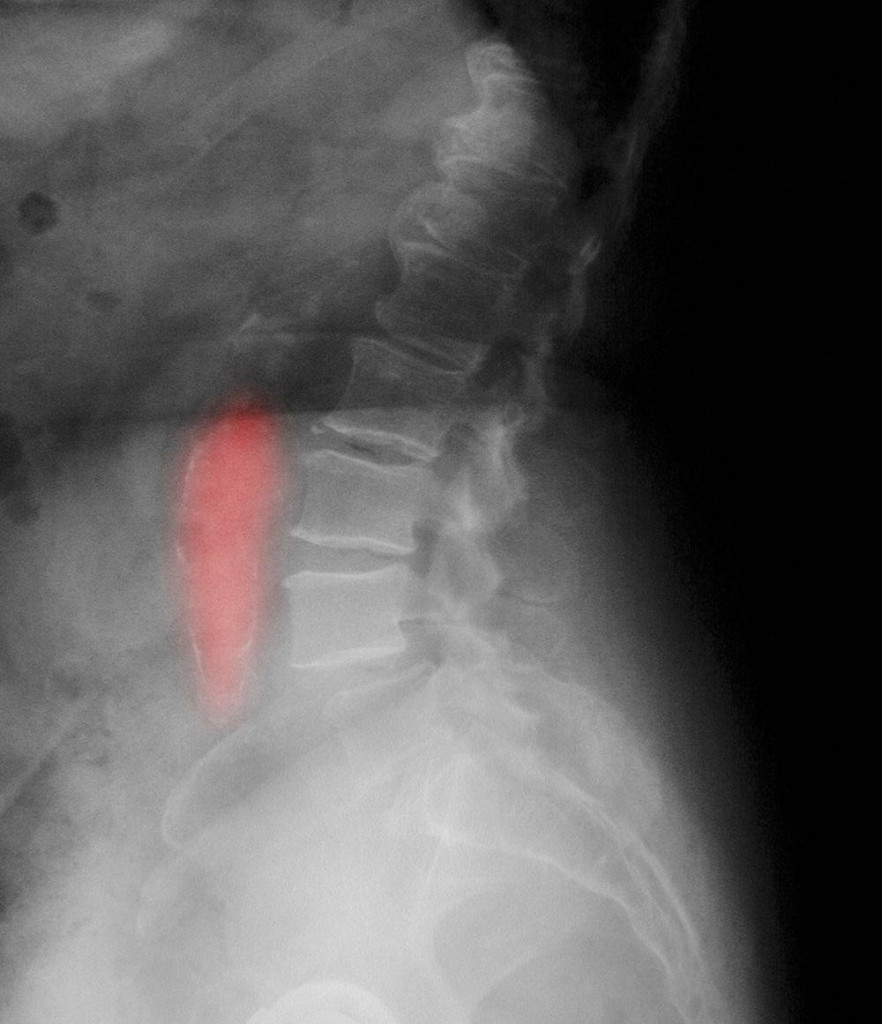

Kada se krvni sud, arterija, uveća više od 50% svoje normalne širine možemo govoriti o aneurizmi. Najčešća njena lokalizacija je u trbušnom delu gde normalno prečnik aorte iznosi od 16-20 mm. Kada prečnik pređe 30 mm možemo govoriti o početnom stadijumu aneurizme abdominalne aorte. Ovo širenje aorte dešava se postepeno i traje godinama.

Posebno zabrinjava porast prečnika od 5 mm godišnje kada se često brzo odlučujemo za operativno lečenje. Pogađa češće muškarce, ali se u poslednje vreme sve češće pronalazi i kod žena. Starosna dob pacijenata je obično u sedmoj deceniji i kasnije, ali se sve češće viđa i kod ljudi u pedesetim godinama.

Jedna od karakteristika abdominalne aneurizme jeste da ona svojim pulsacijama znatno oštećuje tela kičmenih pršljenova gde može da dovede do stanja koje imitira bolesti kičme i međupršljenskih diskova. Ovo naglašavam, jer neretko ovi pacijenti gube vreme u dijagnostici i lečenju bolesti kičmenog stuba. Na kraju, preporuka bi bila da svi ljudi stariji od 55 godina idu jednom godišnje na pregled trbuha ultrazvukom da bi se eventualno otkrila aneurizma u svom početnom stadijumu. Takođe bi se kontrolama trebali podvrgnuti ljudi koji imaju bliskog srodnika koji je imao aneurizmu jer pojava porodične sklonosti nije tako retka. Faktore rizika bi trebalo svesti na minimum uz redovno uzimanje adekvatne terapije za hronične bolesti.